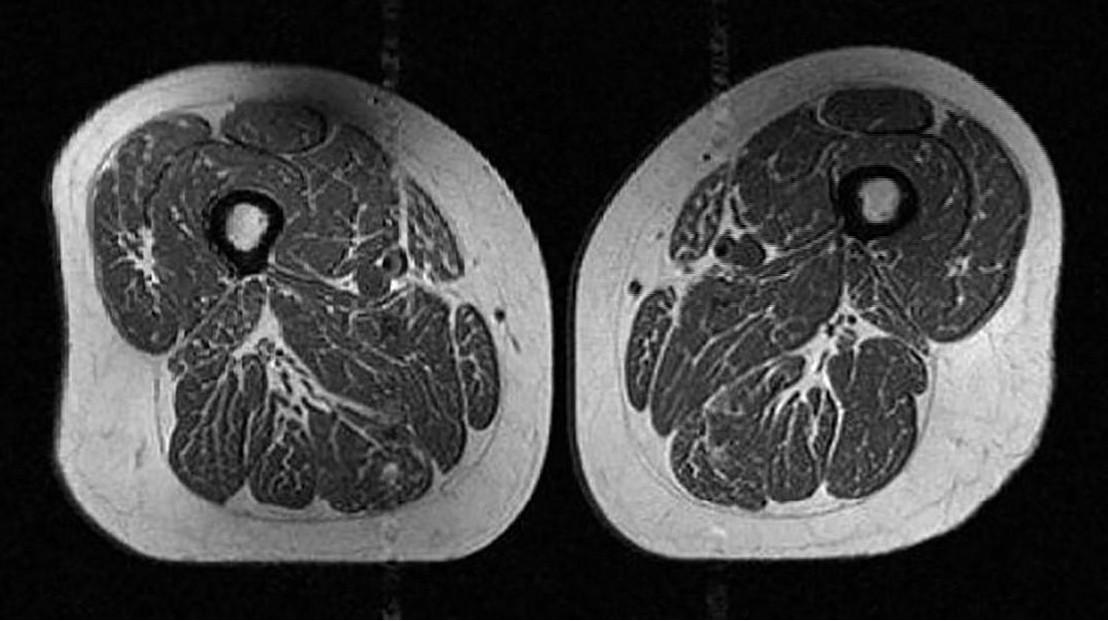

Исследование, опубликованное в журнале Radiology, проанализировало данные МРТ 615 человек. В среднем участникам было 60 лет, а их ИМТ (индекс массы тела) составлял 27 (избыточный вес).

Выяснилось, что количество калорий, потребляемое участниками, похоже, не имело значения. По словам соавтора исследования доктора Томаса Линка, чем больше ультрапереработанных продуктов ел человек, тем больше жира было в его мышцах, независимо от общего калоража.

Хотя исследование не доказывает прямую причинно-следственную связь, ассоциация прослеживается четко. Однако хорошая новость в том, что при переходе на здоровое питание и спорт качество мышц можно улучшить.